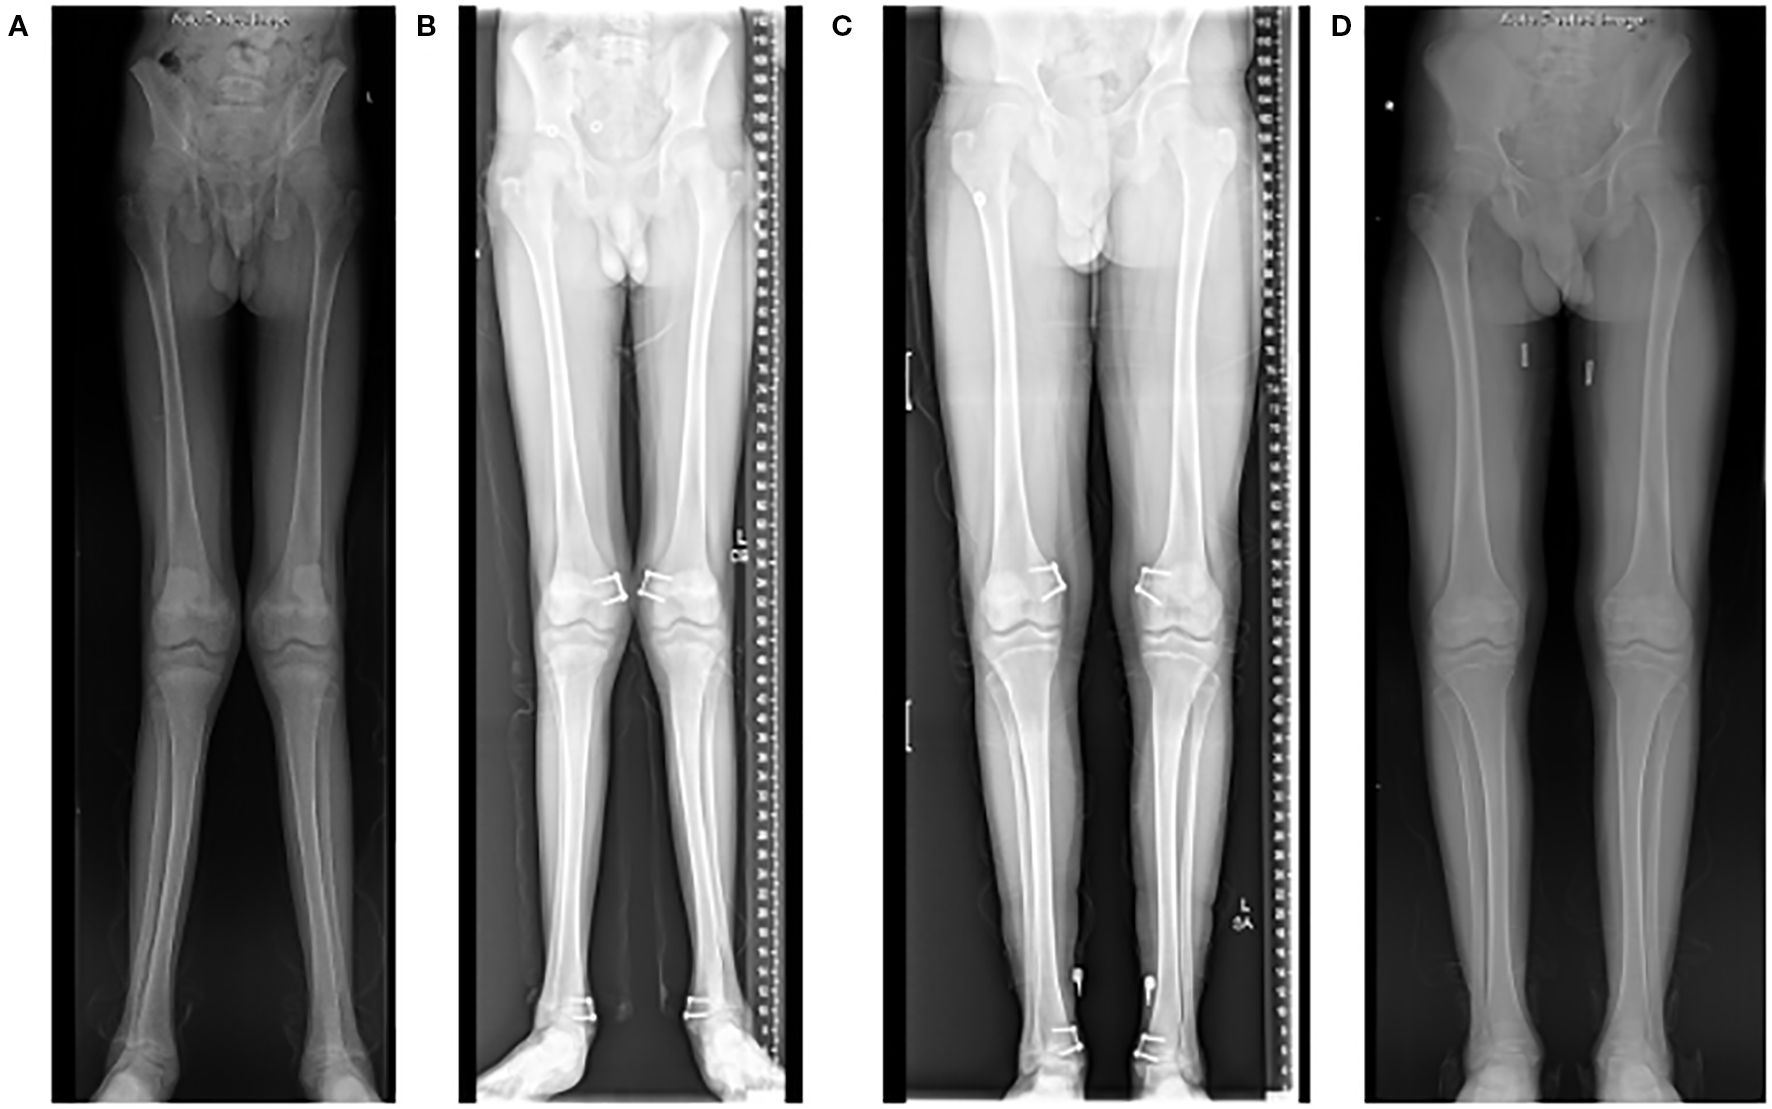

In skeletally immature patients, guided-growth surgery is preferred, if possible, as it is much less invasive and has a relatively short recovery period, especially compared to formal osteotomies and deformity correction. Guided growth procedures capitalize on the growth of the long bones to correct deformity and prevent further progression. Guided growth can be utilized when the child has at least 2 years of growth remaining in mild to moderate long bone deformities. Guided growth surgery involves a temporary hemiepiphysiodesis using small plates and screws that tether the physis on the convex side of the deformity, i.e. laterally in genu varum and medially in genu valgum. The hardware tethers the convex side of the physis and acts as an extraphyseal fulcrum, allowing the opposite (or concave) side of the physis to continue growing. Once satisfactory deformity correction has been achieved, the hardware is removed to prevent overcorrection and to allow for continued balanced growth (Figure 2).

Figure 2. Radiographs of a 15-year-old who presented with significant genu valgum (“knocked knees”) (A). He underwent a guided-growth procedure using tension band plates on the medial side of both his distal femur and distal tibia physes (B). The hardware was removed 2 years after the procedure once satisfactory deformity correction was achieved (C, D).